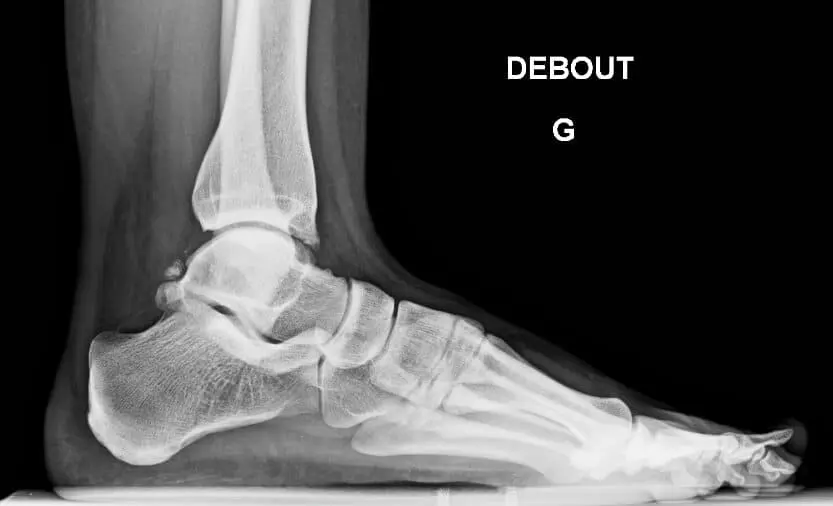

Vous présentez et souffrez d’une douleur de la région postérieure de la cheville.

La douleur peut être ressentie comme fulgurante en descendant une rue en pente ou un escalier, ou lors de la pratique des mouvements spécifiques.

La limitation des mouvements et des mobilités est rare. Contrairement à la région du cou-de-pied ou antérieure de la cheville, la région postérieure est plus profonde et recouverte de parties molles plus épaisses, ce qui complique la tâche pour reconnaître spécifiquement les douleurs.

Cependant, certains tests cliniques, comme fléchir brusquement le pied vers le sol, tourner le pied en équin extrême, …peuvent déclancher les douleurs habituellement ressenties.